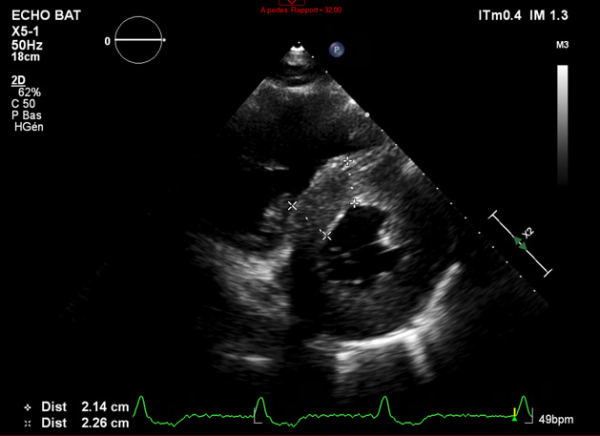

Figure 2 : Échocardiographie 2D Coupe parasternale petit axe (mesure des parois VG)

- Ventricule gauche non dilaté, hypertrophie concentrique symétrique majeure non-obstructive, hypokinésie globale, aspect scintillant du myocarde

- FEVG 45- 50 %

- Pressions de remplissage VG probablement élevées

- Dilatation bi-atriale marquée (OG 54 ml/m²)

- Fuite mitrale centrale modérée, épaississement des valves

- Ventricule droit non dilaté modérément hypertrophique

- Fonction systolique VD diminuée

- Hypertension pulmonaire peu probable (Vmax IT 2,85 m/s)

- Décollement péricardique minime inférieur